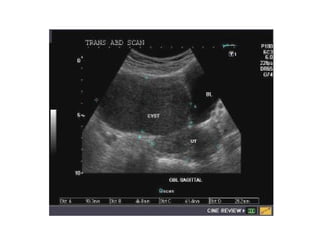

Normal Uterus–Transabdominal. Longitudinal scan through the urine-filled

bladder (B) demonstrates a normal adult uterus with smooth contours, pear

shape, and well-defined bright endometrial echo (open arrow). The cervix (arrow)

is recognized at the junction of imaginary lines drawn through the long axis of the

uterus and the long axis of the vagina (between arrowheads). This uterus is

anteverted.